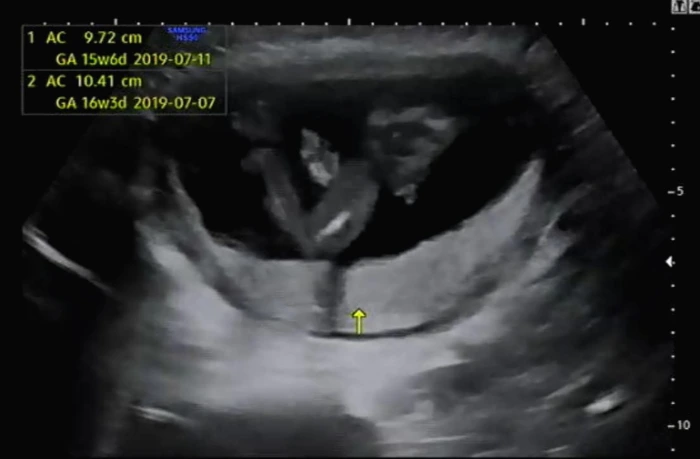

법적으로는 성별을 확인하는 시기가 32주이지만 일반적으로 16주 차가 되면 태아의 생식기가 구별이 확실해지면서 병원에서 알려준다. 초음파를 확인하기 위해 누워 2차 기형아 검사를 위해 태아의 머리둘레 등을 확인하고 마지막에 태아의 배 아랫부분을 확인했다.

화살표 위로 정확히 보이는 삼각점으로 인해 의사가 말하기 전에 나는 아들임을 알아차렸다. 순간적으로 나도 모르게 '헉'이라는 소리가 나왔는데 의사가 웃으면서 "딸이시길 바라셨나 봐요?"라고 이야기를 해왔다.

가끔 성별 반전으로 16주 차에 알게 된 성별이 바뀌는 경우도 있다고 하는데, 내가 봐도 떡하니 보이는 삼각점으로 우리 부부에게는 성별 반전이 없을 것 같았다.